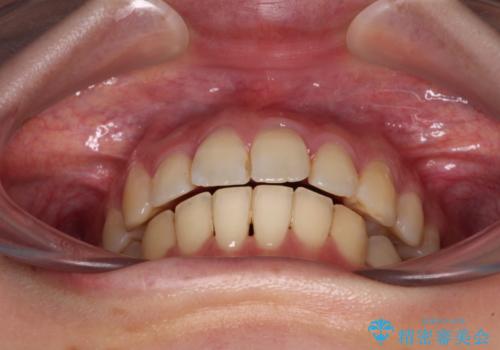

奥歯の咬み合わせはしっかりと改善され、前歯の突出感も改善されました。

- 前歯の突出感を気にして来院された患者様です。